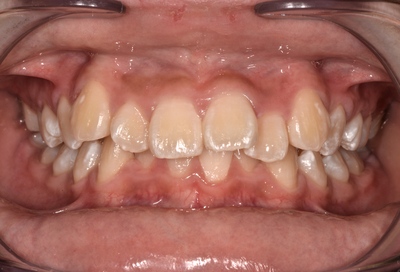

初診時中学3年生

術前

変則的であるが、上顎第一小臼歯2本抜歯し、矯正治療行った。

抜歯後3ヶ月は通常のブラケット+ワイヤー矯正行い、その後インビザラインで治療。

(抜歯スペースを詰めるための歯牙平行移動は、インビザラインは苦手なため)

治療期間10ヶ月。